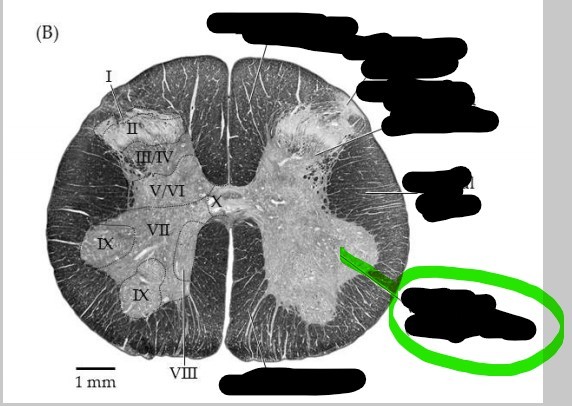

Spinal cord - lateral column

slight protrusion of gray matter of spinal cord into the lateral funiculus of either side; present only in the thoracic and upper lumbar